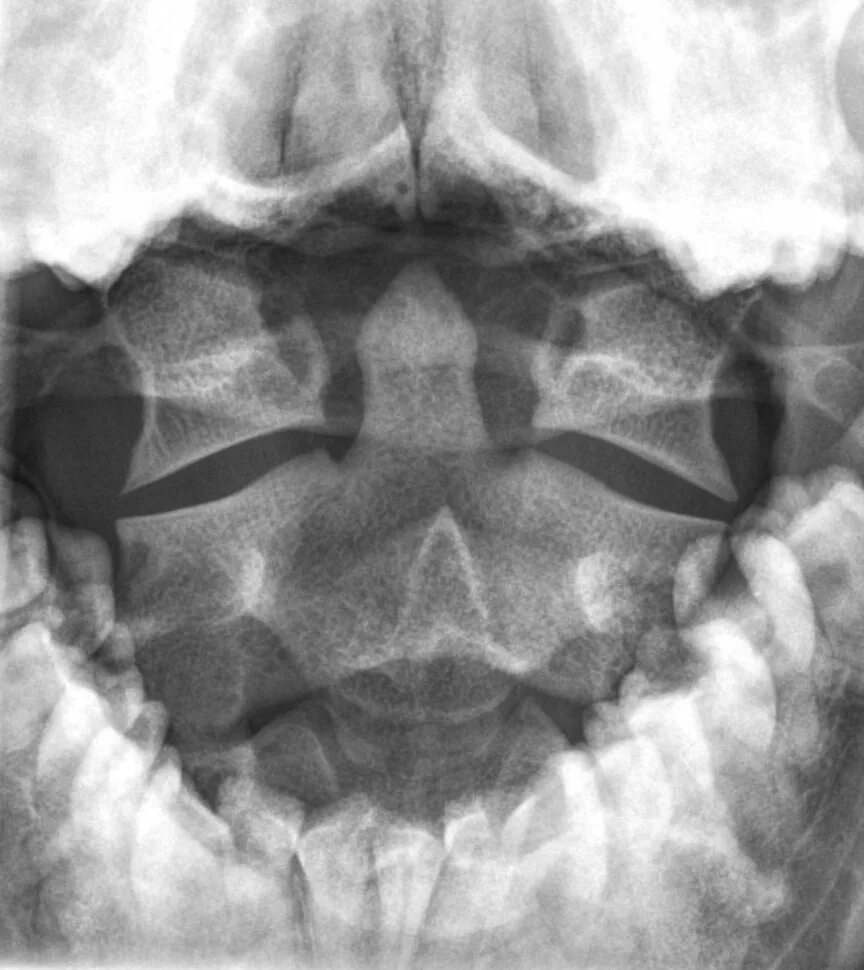

Dens axis